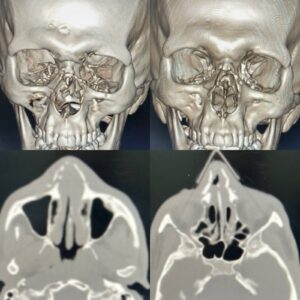

وأوضح وكيل الوزارة أن المريض وصل إلى قسم الطوارئ في حالة حرجة، حيث تبين وجود تهتك شديد بعظام وأنسجة الوجه، مع انمحاء شبه كامل لمعالم الأنف، واندماج بين الفم والأنف، وفقدان الفصل بين مجرى التنفس ومجرى الطعام، ما استدعى التدخل الفوري لإنقاذ حياته.

ومن جانبه، أوضح الدكتور أحمد معتمد عامر، استشاري ورئيس قسم جراحة الوجه والفكين، أنه تم التعامل مع الحالة بشكل عاجل فور وصولها، حيث جرى تأمين مجرى الهواء كأولوية قصوى، ثم نقل المريض إلى غرفة العمليات لإجراء تدخل جراحي دقيق استمر نحو 5 ساعات متواصلة.

وأشار إلى أن الجراحة تضمنت فك الاندماج بين الفم والأنف وإعادة المسارات التشريحية الطبيعية، إلى جانب إعادة بناء الهيكل العظمي للأنف وترميم الأنسجة الرخوة، بما ساهم في استعادة الشكل التشريحي للوجه، والفصل بين الوظائف الحيوية كالتنفس والكلام وتناول الطعام.